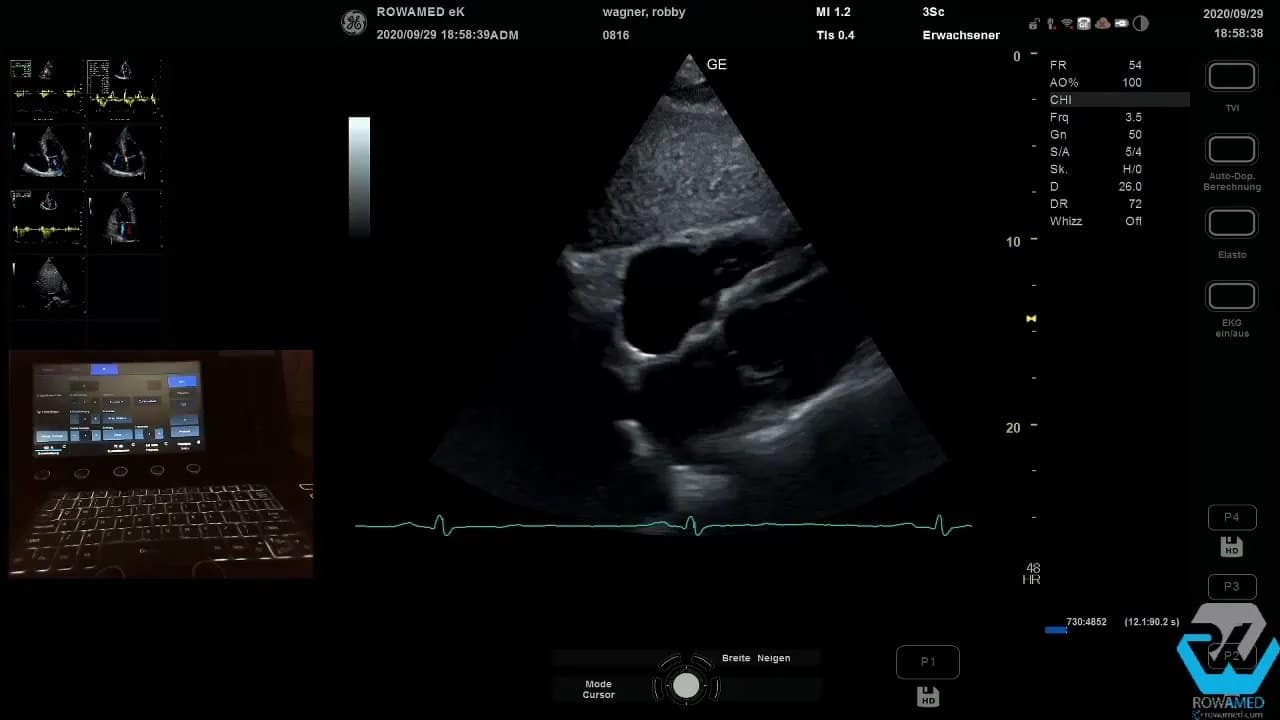

Step 14: Die subkostale Ebene zum Schluss gezielt einsetzen

Die letzte Standardebene ist die subkostale Anlotung. Hier beurteilen Sie zum einen den venösen Füllungszustand. Schlanke, nicht gestaute Lebervenen sprechen gegen Rechtsherzinsuffizienz und gegen eine relevante Volumenüberladung. Zugleich lässt sich daraus der zentrale Venendruck abschätzen, was wiederum für die Berechnung des pulmonalarteriellen Drucks wichtig ist.

Im gezeigten Fall waren die Lebervenen schlank, der ZVD wurde mit 5 mmHg angenommen, passend zum insgesamt unauffälligen Rechtsherzbefund.

Zum anderen erhalten Sie hier den subkostalen Vierkammerblick. Dieser ist besonders wertvoll für die Beurteilung des Vorhofseptums. Der Grund ist physikalisch simpel: Das Septum liegt in dieser Projektion günstig zur Schallrichtung. Deshalb lassen sich Vorhofseptumdefekte oder Links-Rechts-Shunts hier oft besser erkennen als im apikalen Vierkammerblick.

Ein Links-Rechts-Shunt würde sich als gerichtetes Farbsignal vom linken in den rechten Vorhof zeigen. Im beschriebenen Befund war ein solcher Shunt nicht nachweisbar.

Auch Mitral- und Trikuspidalklappe können in dieser Ebene noch einmal mit Farbe überprüft werden. Dass die Insuffizienzen hier nahezu nicht auffielen, passte sehr gut zur Einschätzung als geringer, klinisch wenig bedeutsamer Befund.